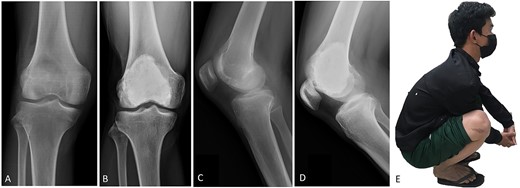

(A, C) Case no. 5: female, 23 years of age with GCTB at the distal femur without subchondral bone involvement, Campanacci grade III. (B, D) Radiograph at 81 months after extended curettage with hydrogen peroxide, phenol and cementation. (E) MSTS score 93%.